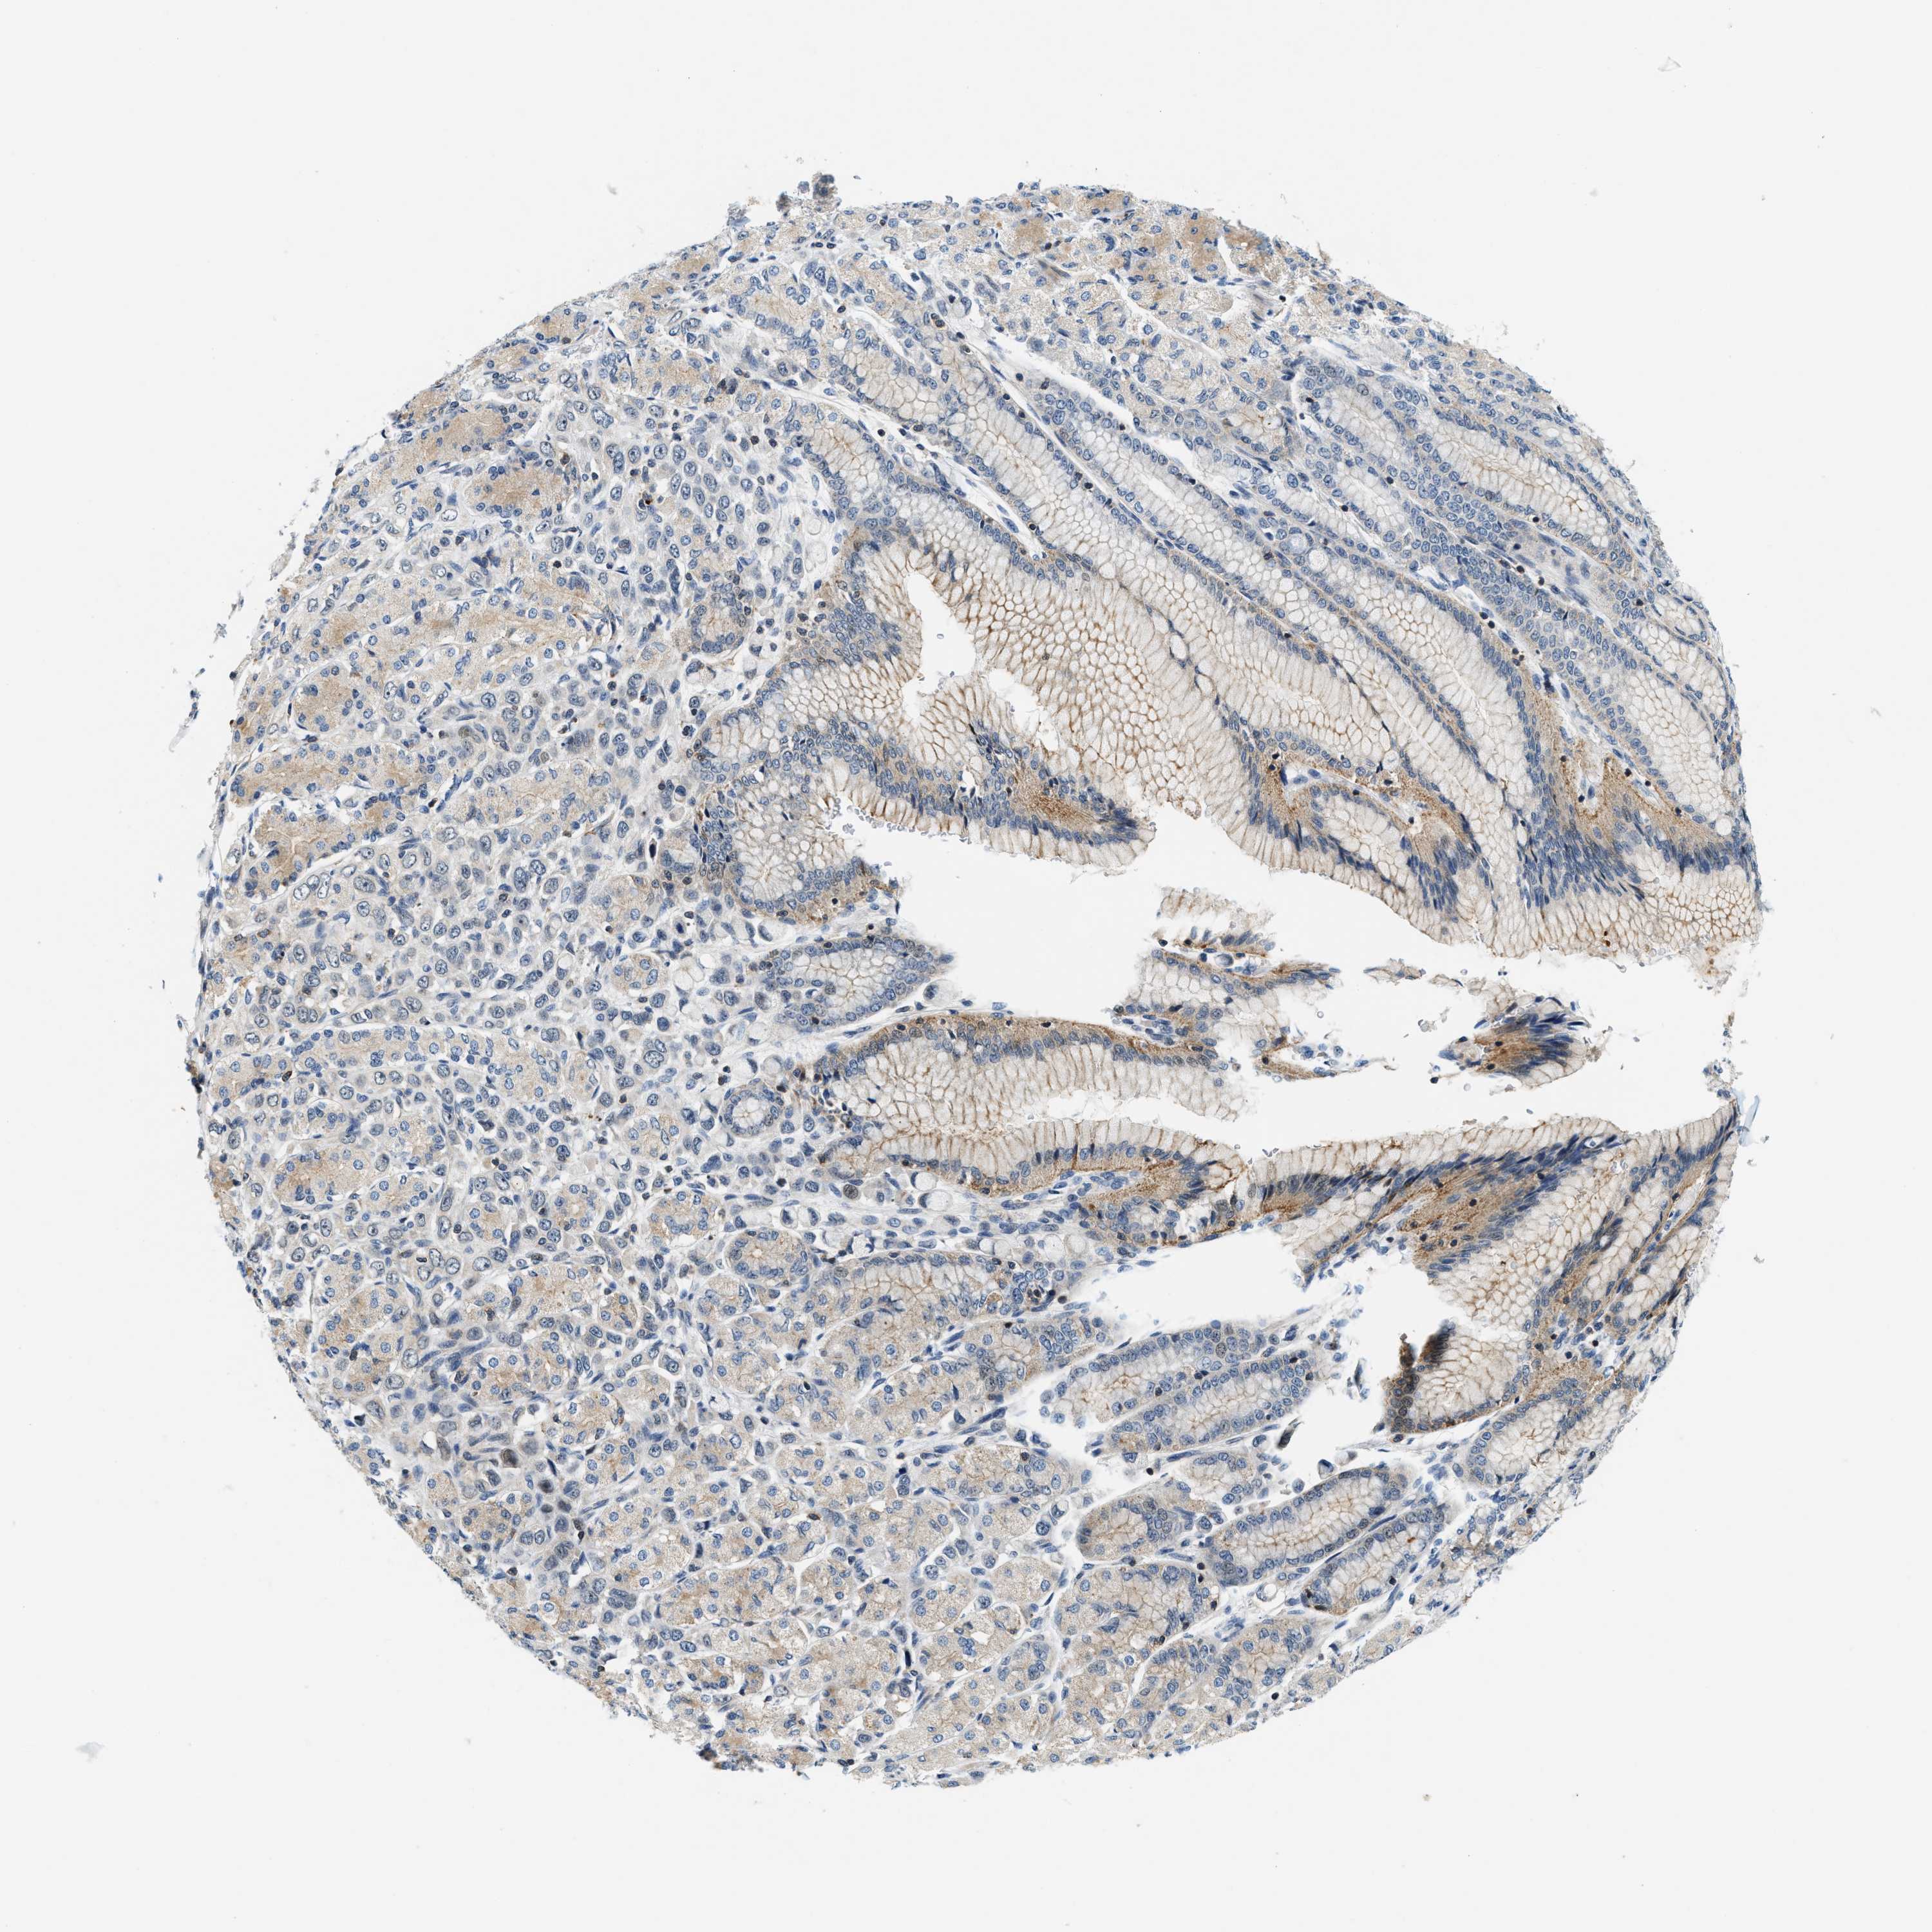

STOMACH CANCER - Protein expressioni

A mouse-over function shows sample information and annotation data. Click on an image to view it in a full screen mode. Samples can be filtered based on level of antibody staining by selecting one or several of the following categories: high, medium, low and not detected. The assay and annotation is described here.

Note that samples used for immunohistochemistry by the Human Protein Atlas do not correspond to samples in the TCGA dataset.

Antibody stainingi

Antibody staining in the annotated cell types in the current human tissue is reported as not detected, low, medium, or high, based on conventional immunohistochemistry profiling in selected tissues. This score is based on the combination of the staining intensity and fraction of stained cells.

Each image is clickable and will lead to virtual microscopy that enables deeper exploration of all samples and also displays staining intensity scores, fraction scores and subcellular localization as well as patient and tissue information for each sample.

Antibody HPA021318

Antibody HPA021319

Staining

High

Medium

Low

Not detected

Intensity

Strong

Moderate

Weak

Negative

Quantity

>75%

75%-25%

<25%

None

Location

Nuclear

Cytoplasmic/membranous

Cytoplasmic/membranous,nuclear

Adenocarcinoma, NOS